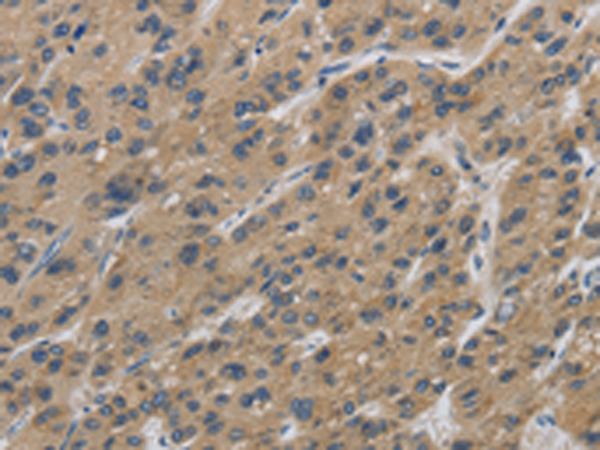

分类: 科研抗体货号: P11833别名: EPF; CPN10; GROES; HSP10应用: IHC反应种属: Human, Mouse, Rat